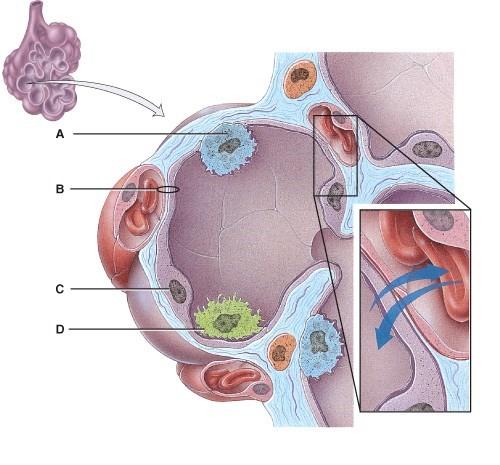

This provides disease resistance within the lungs.

- A

- B

- C

- D

- None of the above

D

Which cells are the main sites of gas exchange?

- A

- B

- C

- D

- All of the above

C

Which cell secretes surfactant?

- A

- B

- C

- D

- None of the above

A